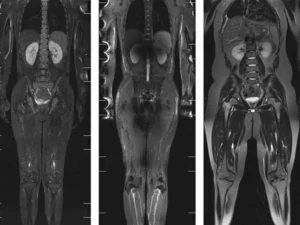

Tüm vücut MR, manyetik rezonans görüntüleme teknolojisi kullanılarak vücudun tamamının ayrıntılı bir şekilde taranmasıdır. Radyasyon içermeyen bu yöntem, manyetik alan ve radyo dalgaları yardımıyla organların ve dokuların yapısını detaylı bir şekilde gösterir. Doktorlar, bu görüntüleri kullanarak hastalıkları teşhis eder ve tedavi planlarını oluşturur.

Tüm vücut MR, kanser şüphesi olan hastalarda, inflamatuar hastalıklarda, enfeksiyonların yayılımını belirlemek için ve dejeneratif hastalıkların teşhisinde kullanılır. Ayrıca, kronik ağrıların kaynağını tespit etmek, sinir sistemi hastalıklarını ve damar problemlerini değerlendirmek amacıyla da uygulanabilir.

Tüm vücut MR ile kanser türleri, tümörlerin yayılımı, inflamatuar hastalıklar, enfeksiyonlar, dejeneratif hastalıklar, sinir sistemi bozuklukları ve damar hastalıkları teşhis edilebilir. Bu yöntem, özellikle erken teşhis gerektiren hastalıklarda büyük önem taşır ve doktorların doğru tedavi yöntemini belirlemelerine yardımcı olur.